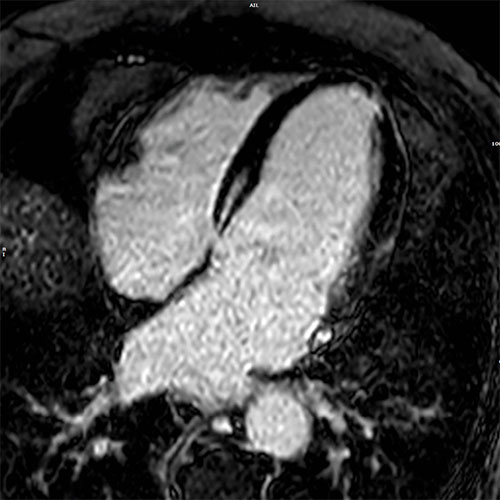

Cardiac MR images of a patient with non-ischemic cardiomyopathy showing delayed enhancement and severe mitral regurgitation.

PSIR - 4 chamber view

bTFE - 4 chamber view